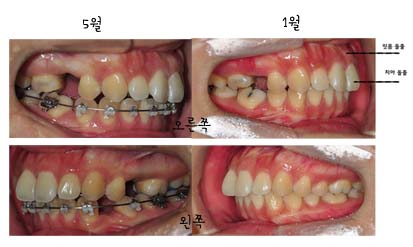

다음은 초기와 현재5월의 상태를 비교해보았어요 좀 변화가 보이나요~??

상악의 잇몸부분이 조금 들어간것같기두하구~